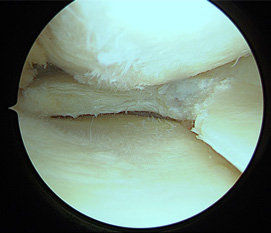

• 画像:損傷後内側半月板関節鏡画像

損傷後内側半月板関節鏡画像

• 画像:部分切除後内側半月板関節鏡画像

部分切除後内側半月板関節鏡画像